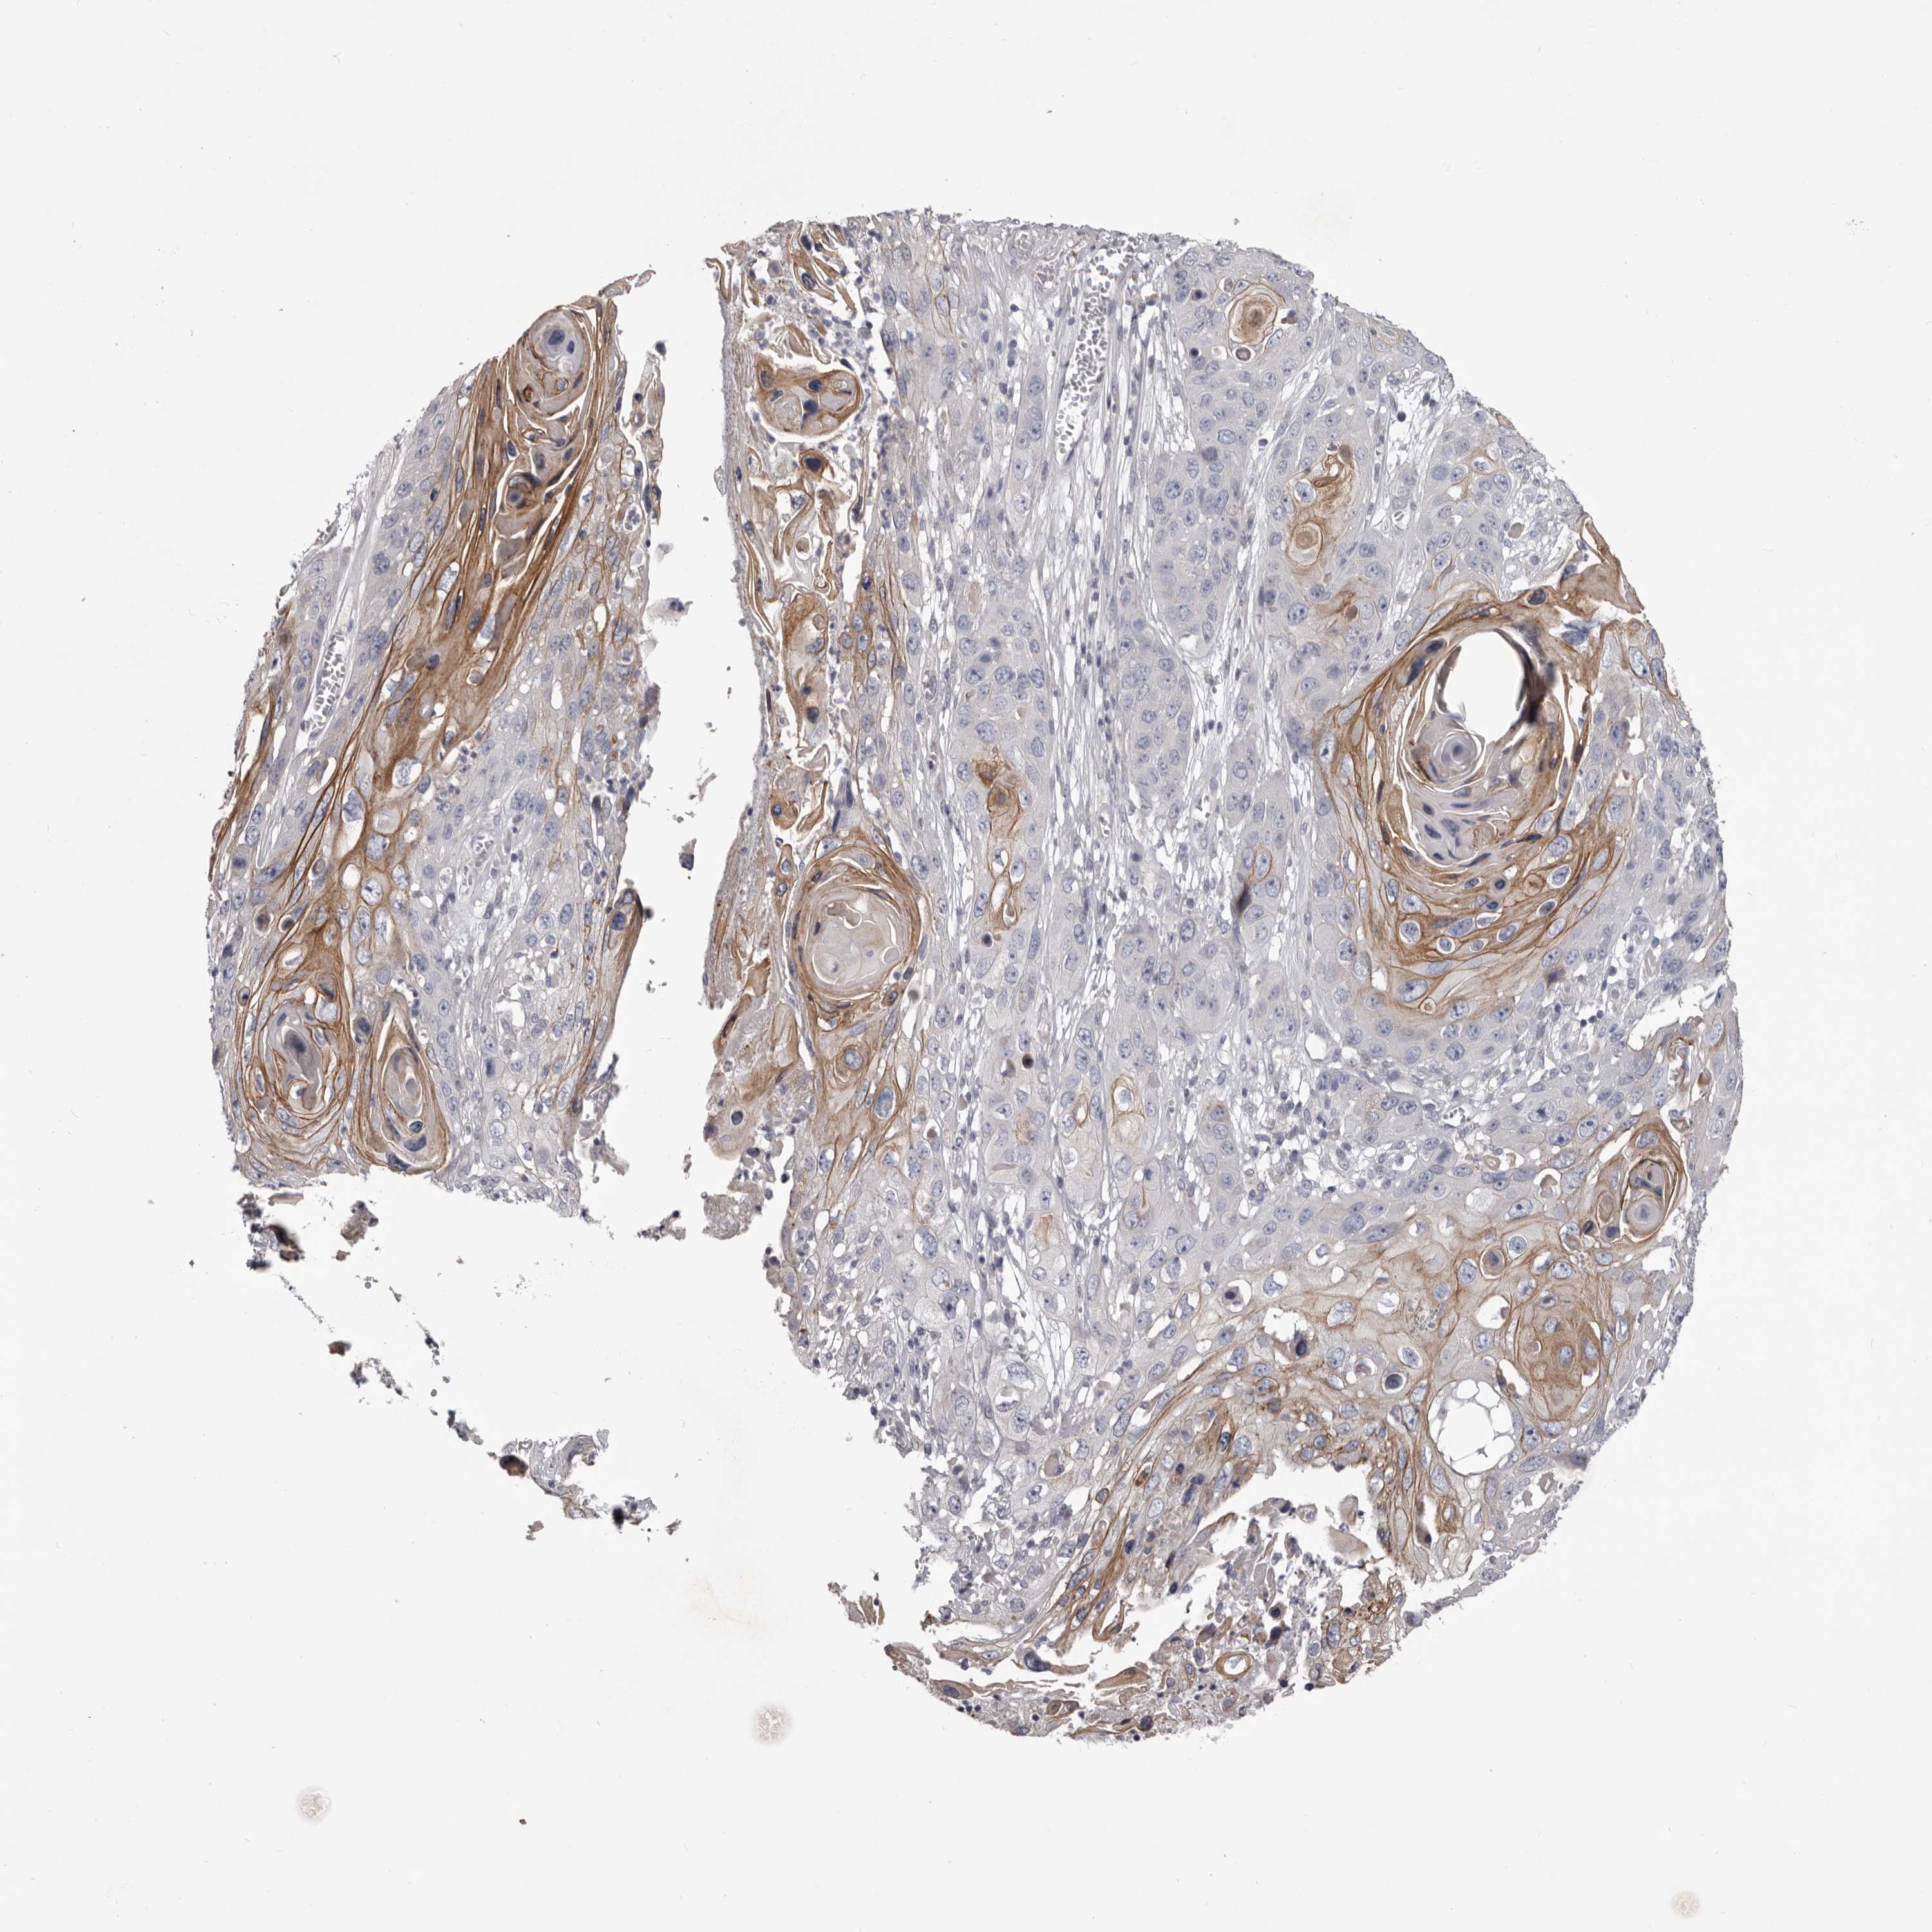

CANCER SKIN CANCER Show tissue menu

Basal cell and squamous cell cancer

SKIN CANCER - Protein expressioni

A mouse-over function shows sample information and annotation data. Click on an image to view it in a full screen mode. Samples can be filtered based on level of antibody staining by selecting one or several of the following categories: high, medium, low and not detected. The assay and annotation is described here.

Each image is clickable and will lead to virtual microscopy that enables deeper exploration of all samples and also displays staining intensity scores, fraction scores and subcellular localization as well as patient and tissue information for each sample.

Antibody HPA028934

Staining

High

Medium

Low

Not detected

Intensity

Strong

Moderate

Weak

Negative

Quantity

>75%

75%-25%

<25%

None

Location

Nuclear

Cytoplasmic/membranous

Cytoplasmic/membranous,nuclear

Basal cell carcinoma

Squamous cell carcinoma, NOS

Squamous cell carcinoma, metastatic, NOS